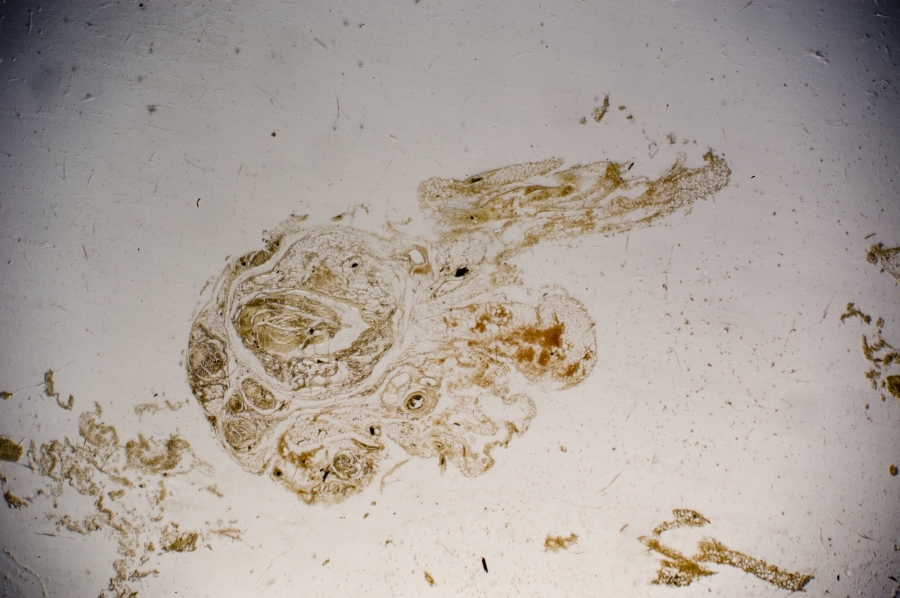

Image Filename: 36931_4541-1

36931_4541-1

container invno 36931

specimen id 4541